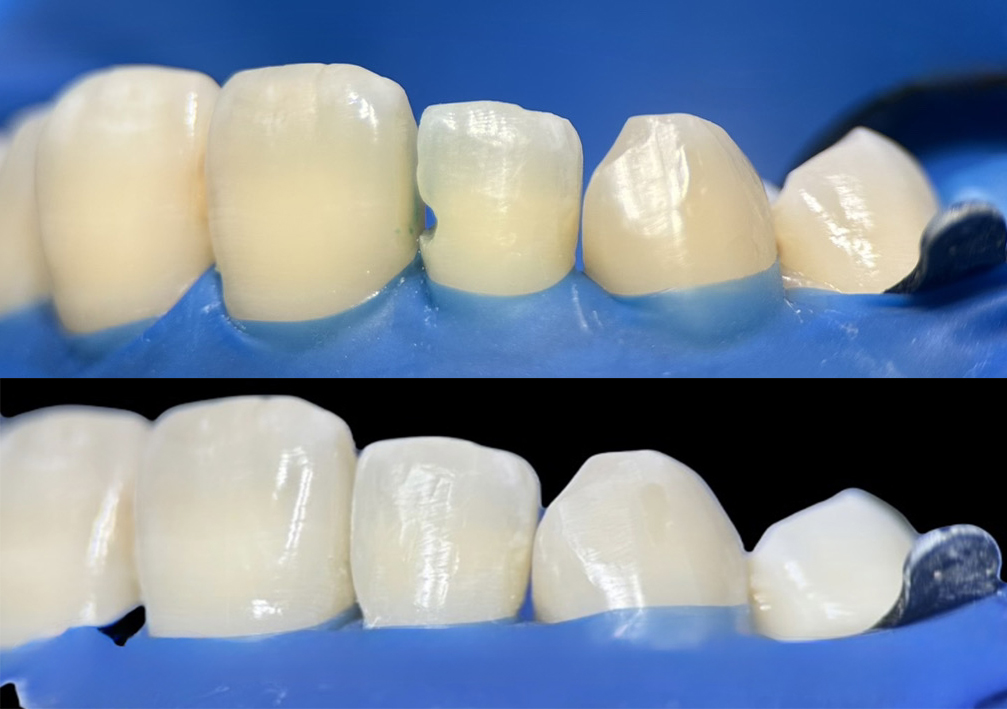

- 前歯のすきっ歯

歯と歯の間の隙間をダイレクトボンディングで自然な見た目に修復しています。